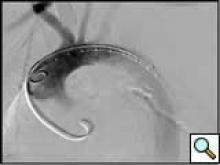

Optimal imaging of the thoracic aorta is obtained by advancing a 90cm pigtail catheter to the level of interest, which is usually in the proximal aortic arch. The power injector is connected using sterile tubing and all tubing in de-aired thoroughly. Thoracic aortic contrast is set to 20ml/sec for 40ml total and the patient is instructed to hold their breath and the aortogram is performed.

Angulation of the C-Arm is essential for fluoroscopic evaluation of the arterial tree. The basic projections are listed in Table 1. These suggested projections optimize full visualization of the artery and are necessary for correct assessment of angulation, tortuosity, and length measurements. An example of the thoracic aortic arch illustrated at different angulations is demonstrated in Figure 2.